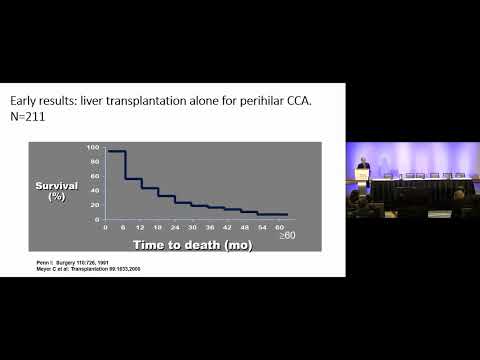

KN02: Contemporary Management of Hilar Cholangiocarcinoma

Keynote Lecture 02: Contemporary Management of Hilar Cholangiocarcinoma